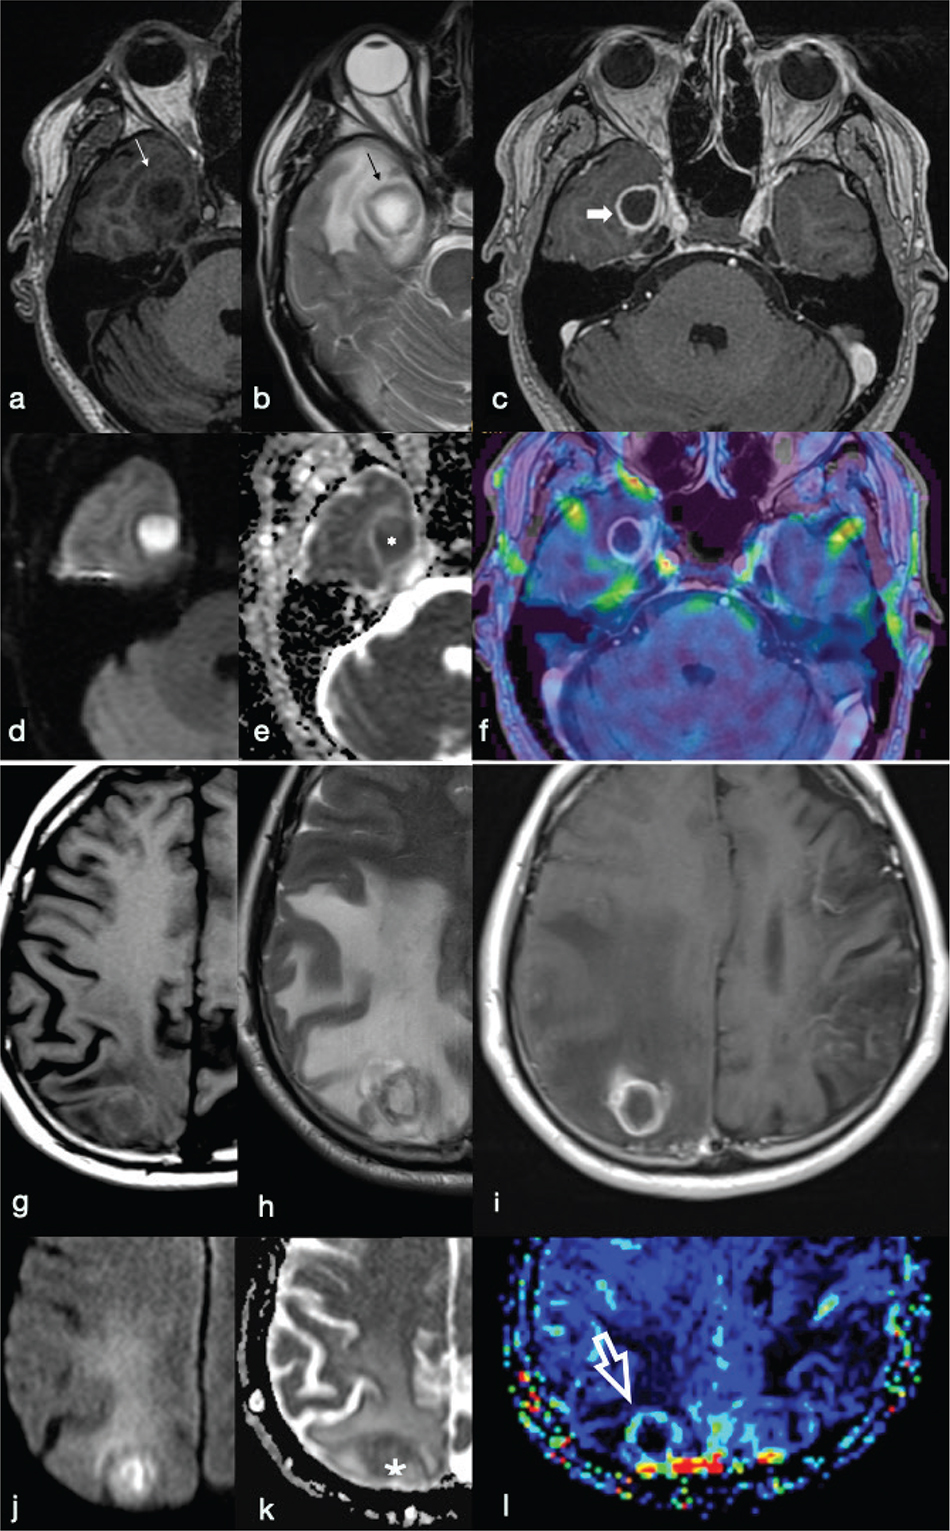

PWI provides information about the vascularisation of a lesion. Usually, PWI in pyogenic BA demonstrate low relative cerebral blood volume (rCBV) in the capsule, whereas necrotic brain tumours show elevated rCBV as a result of neoangiogenesis within the tumour tissue (Figure 11).11 This technique may be useful in the differential diagnosis of ring-like enhancing brain lesions that may mimic BA. These include neoplastic lesions (glioblastoma, metastases) and demyelinating lesions. However, rCBV values may vary according to the stage of the capsule: higher in the early stage than in the late stage in which the fibroblasts are dominant.5,11

FIG 11. Differences between a Pyogenic Brain Abscess (a-f) and a Hypercellular Lung Metastasis (g-l). The peripheral ring of the abscess and cystic metastasis are hyperintense on T1w (a, g), hypointense on T2w (b, h) and show complete rim enhancement on T1w+Gd (c, i) images. The core of the lesion is hypointense on T1w (a, g), hyperintense on T2w (b, h) and may show restricted diffusion on DWI (d, j) and ADC maps (e, k). However, dynamic susceptibility contrast enhanced PWI does not show evidence of increased relative cerebral blood volume (rCBV) in the gadolinium-enhancing rim of the abscess (f) in comparison to the increased perfusion of the enhancing rim appreciable in the metastasis (white open arrow in l).